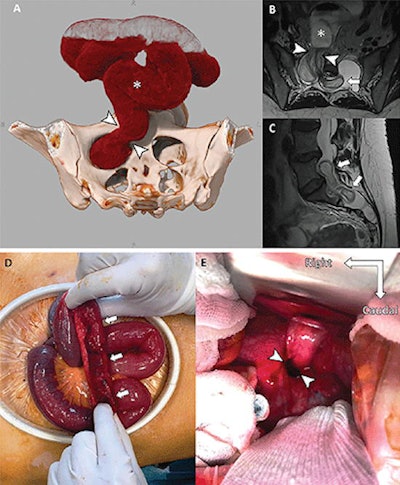

The 2022 winner was from an article published June 14, 2022, titled, "Intradural Small Bowel Herniation." by neuroradiologists at the Francois Mitterrand University Hospital in Dijon, France. The cinematic 3D-rendered image depicts unusual pathology in a case of a 38-year-old woman with Marfan syndrome who underwent resection for a presumed right ovarian cyst.

Images of a 38-year-old woman with Marfan syndrome who was diagnosed with intradural small bowel herniation through a torn right S1 dural ectasia. (A) Oblique global illumination rendering of abdominal CT scan after semiautomatic segmentation of the enlarged afferent small bowel (*). The hernia orifice (arrowheads) separates the peritoneal cavity and the intradural space. (B, C) T2-weighted MRI scans in (B) axial and (C) sagittal planes show the herniated loop (arrowheads in B) of small bowel (* in B) ascending at L5-S1 (arrows), causing significant compression of the adjacent cauda equina nerve roots. Image courtesy of Radiology.The first runner-up is an article published August 3, 2021, titled, "Myocarditis Following COVID-19 Vaccination," by a group at University Hospital Bonn, Venusberg-Campus 1, 53127 Bonn, Germany. This is the third consecutive year in which a COVID-related image was honored among top contenders.